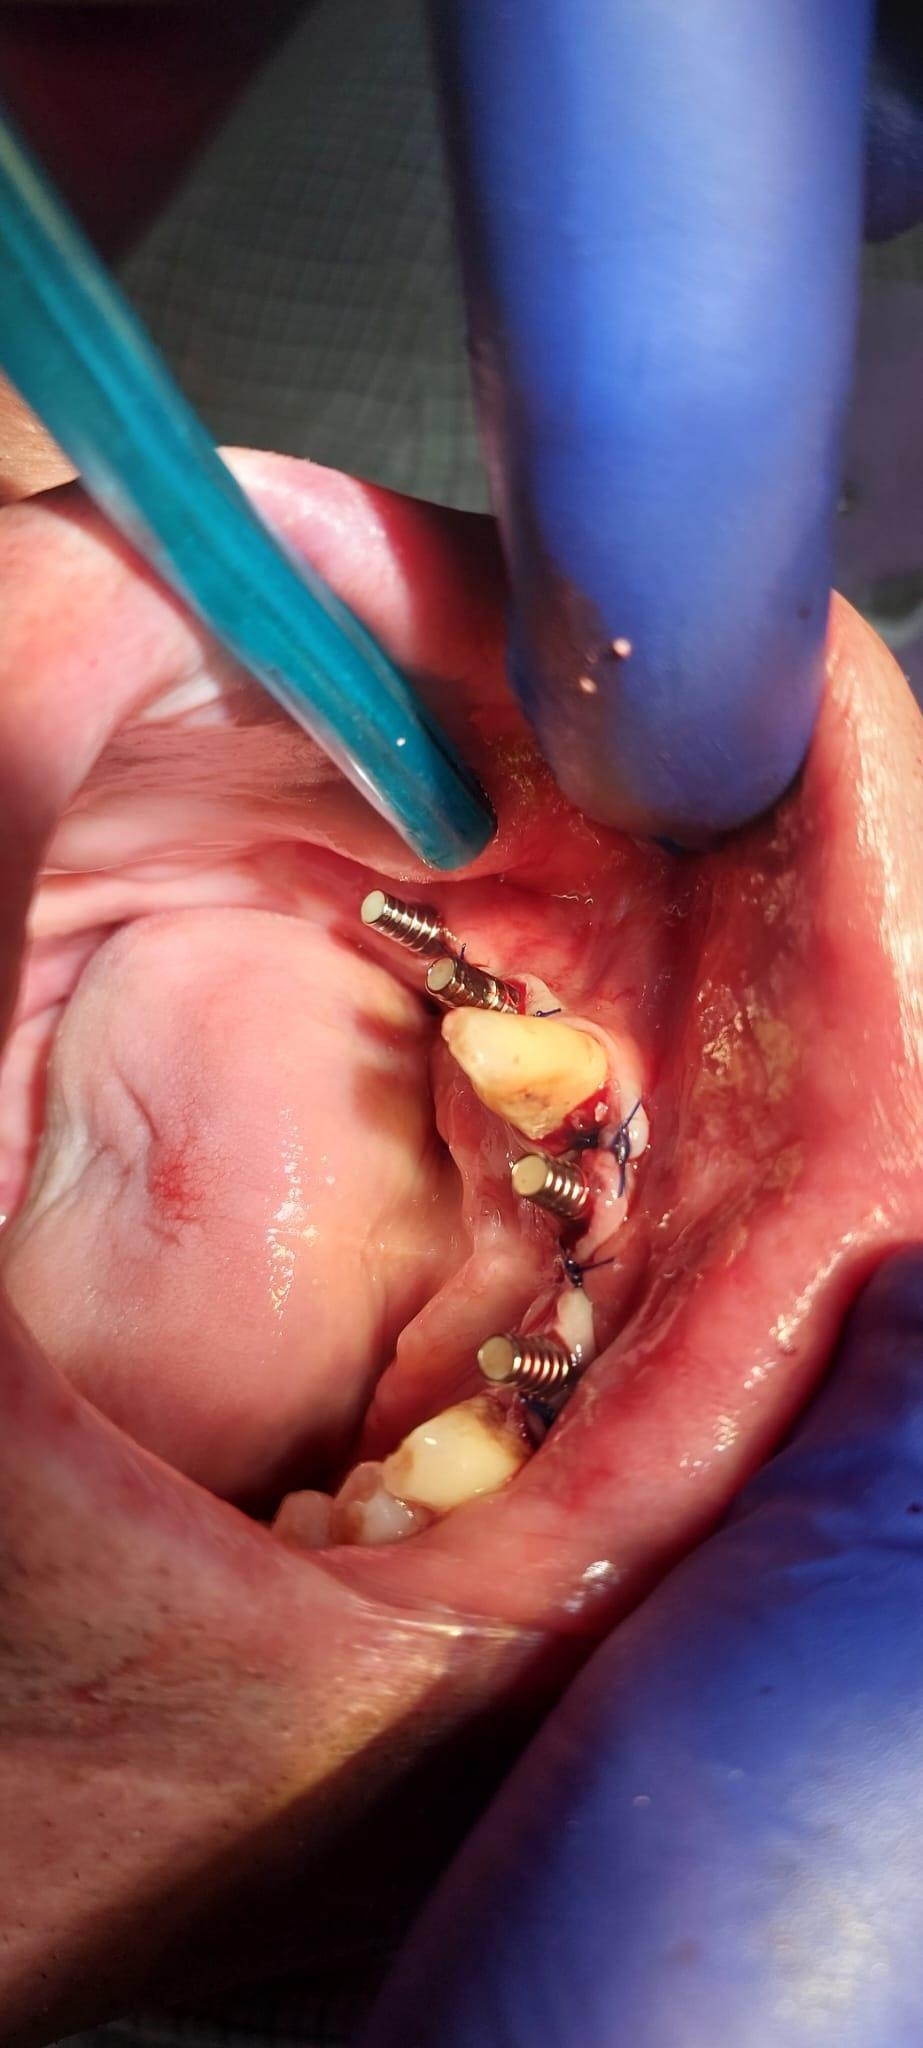

Boala parodontala are un caracter progresiv. Pentru cazurile mai grave, recomandam tratamentul parodontal chirurgical rezectiv sau regenerativ.

O igiena bucala necorespunzatoare, fumatul, placa bacteriana si alte boli generale, permit bacteriilor sa se dezvolte in cavitatea bucala.